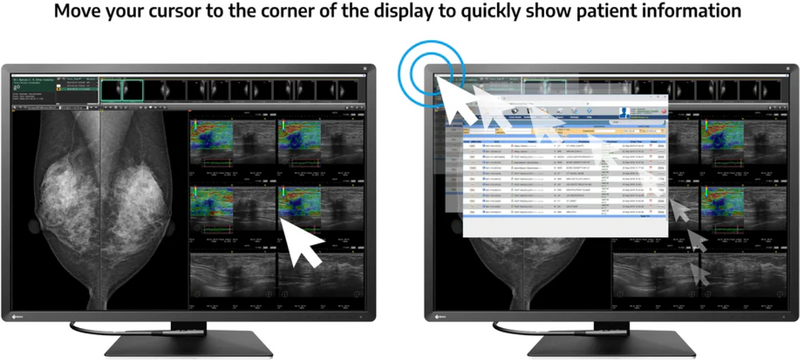

Αναφορά γρήγορων πληροφοριών

Η λειτουργία απόκρυψης και αναζήτησης επιτρέπει στους χρήστες να κρύβουν εύκολα το παράθυρο PINP (Εικόνα στην εικόνα) που δεν χρησιμοποιείται και ανοίγει ξανά, όπως απαιτείται, μετακινώντας τον δρομέα του ποντικιού στην άκρη της οθόνης. Αυτό εξαλείφει την ανάγκη για μια επιπλέον οθόνη, ενώ παράλληλα επιτρέπει γρήγορη και αποτελεσματική προβολή αναφορών ή διαγραμμάτων ασθενών.